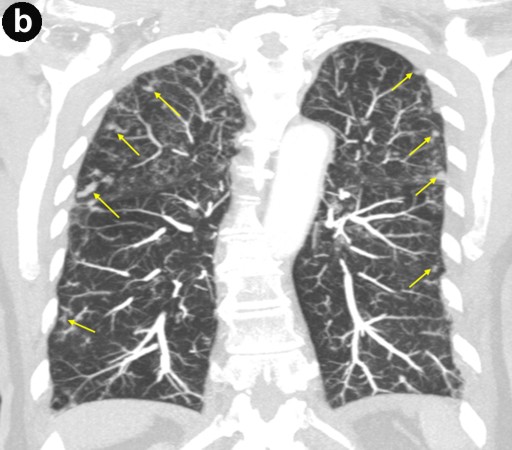

A 79-year-old asymptomatic women was found to have a serum CA 19-9 of 210 U/mL (reference range: 0-37 U/mL) during a general medical examination in 2000; the CEA level was 1.8 ng/mL (reference range: 0-5.0 ng/mL). They were done by her primary care physician because of a family history of breast and ovarian cancers. Computer tomography (CT) and magnetic resonance imaging cholangiopancreatography (MRCP) examinations in 2000, 2001, and 2002 from an outside facility reported stable small cysts at the head of the pancreas. The patient had never smoked or been an alcohol drinker. She had no history of pancreatitis or abdominal trauma. Her past medical history was significant for recurrent pneumonia, partial hysterectomy, and gastroesophageal reflux disease. Upon referral to our institution in 2003, MRCP demonstrated several subcentimeter pancreatic cysts in communication with a non-dilated pancreatic duct; endoscopic cholangiopancreatography (ERCP) revealed a subcentimeter cyst in the pancreatic head, communicating with the main pancreatic duct (Figure 1). No pancreatic abnormalities were seen on endoscopic ultrasound (EUS). High resolution CT of the chest showed bronchiectasis predominately in the right middle lobe and lingula consistent with Lady Windermere syndrome (Figure 2). In 2005, the patient was hospitalized several times with the diagnosis of "community acquired pneumonia." Repeat high resolution CT of the chest showed worsening of bronchiectasis with Mycobacterium avium-intracellulare complex-positive sputum cultures. The Mycobacterium avium-intracellulare complex infection was not treated because the positive cultures were thought to be due to colonization. In 2006, the patient was hospitalized again for pneumonia and triple therapy (rifampin, ethambutol, azithromycin) was started for Lady Windermere syndrome. Due to side effects, the therapy was discontinued after 3 months of treatment.

Figure 2. Lady Windermere syndrome. Axial CT image (a.) shows bronchiectasis (white arrows) in the right middle lobe (RML) and lingula with clustered small nodules (yellow arrows) representing bronchioles filled with mucus, fluid, or pus ("tree-in-bud" appearance). In addition, coronal CT image (b.) shows "tree-in-bud" appearance involving both upper lobes as well as the lower lungs (yellow arrows); this is consistent with Mycobacterium avium-intracellulare complex infection. |